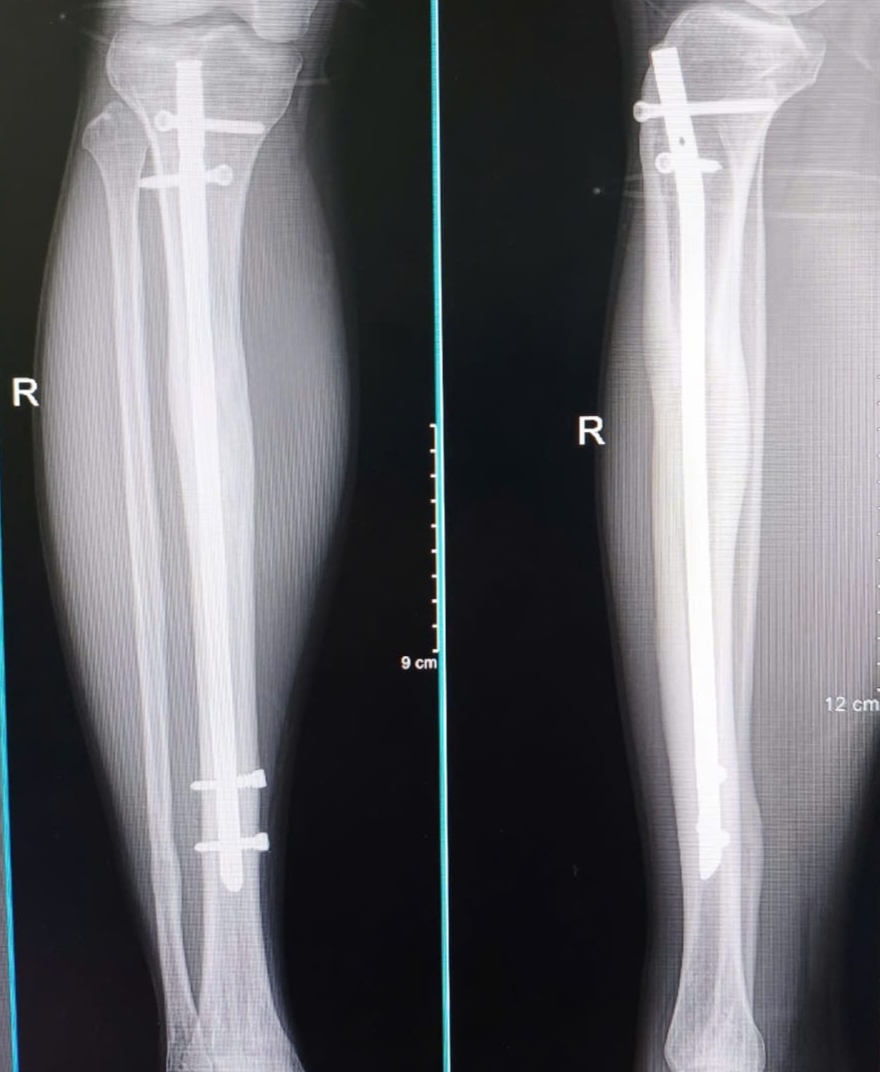

Part 4, ending the lengthening: The time had come where I had reached my desired length. I had opted to go from 7cm down to 6.7, because this was around 20% of my original tibial length. There were however patients who went very much upwards of 7cm, I had met one and we got along quite well. You then stay in your frame for a while longer as the callus (the regenerative structure of your bone) continues to heal. Xrays at this time revealed it as mostly translucent compared to the strong milky white color of the developed bone around it. Eventually I was cleared for frame removal. I knew it’d be a relief to get these things off, but as I was prepped for my second surgery, I ended up crying, I was really fed up with the whole ordeal. The hospital setting, and going in again for another operation really brought the weight and considerations back, but I knew the most challenging parts were behind me. I’ve got to say, the freedom from the frames is amazing, you’re not worried about bumping them into anything, you can roll around in bed, sleep easier, and you start to make the jump from stroller to crutches. From here you gain a whole new degree of freedom, everyday I spent time strolling back and forth with the crutches. Around this time I was transferred to the apartment with the pool and courtyard, and that courtyard became my little slice of heaven. I’d just walk it with crutches around and around, the security guard got so accustomed to my little outings that he introduced himself and told me I was making good progress. One night I had a breakthrough, I was sitting on my bed, practicing these little squats when I stood shakely up, and from there took a step, and then another, sure my gait and posture was far from normal, but my steps felt steady enough that I could just keep on moving on even flooring, I smiled so much just being able to go back and forth without tools for the first time in what felt like forever, and I knew the end was around the corner.

Part 7, Nail removal and then end of my journey: writing this as of now, I am returning for my nail removal. It is a bit surreal visiting the original hospital, greeting and meeting other patients in the middle of their lengthening and being reminded of what was my reality for what felt like so long. But walking up and shaking the hands of patients, none of them realised I’d gone through this until I pulled up my pants to show them the scars. Getting my Xray done, I was happy with the results, the bone of where my osteotomy and distraction took place was as opaque as that of the original bone, the vector of the bone to my eyes also matched the original, a bit thicker in some places, but it’s quite a marvel to see what the human body is capable of in terms of skeletal regeneration. There’s a bit of nervousness to go on to the operating table again, but mostly excitement to be done, to not worry about the complications of having this metal hardware in your legs long term, and utmost a faith that the nail removal is a vastly more simple procedure then inserting it along with the frames and stretching your legs out, the worst part it over, and I’m grateful to close the chapter on this journey, you’re not the same person before and after, I never really visited the limb lengthening forum or watched any of Victor’s videos after I returned home. Your mind goes to different focuses and motivations because you have completed what you set out for. I will post an update on the intricacies of the nail removal, and try my best to answer any further questions, but the Limb Lengthening forum isn’t something I intend to visit again regularly, it is a part of what is quickly becoming the past for me. Images and videos are attached for those curious.